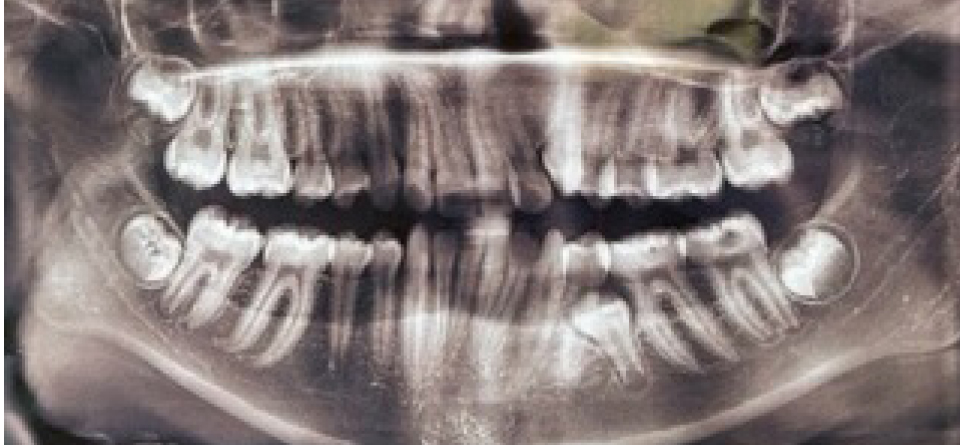

Результаты изучения анамнестических данных показали, что причиной односторонней ретенции вторых премоляров, как на верхней, так и нижней челюсти, было преждевременное удаление вторых молочных моляров на одной из сторон, которое отмечались практически у всех обследованных, что способствовало ретенции второго премоляра (рис. 2).

Рис. 2. Ортопантомограмма у пациентки с ретенцией второго нижнего премоляра слева

В связи с указанным фактом отмечалось перемещение зубов, ограничивающих дефект навстречу друг другу, что способствовало укорочению диагональных, передне-задних и трансверсальных размеров арки и изменению ротационных показателей зубов.